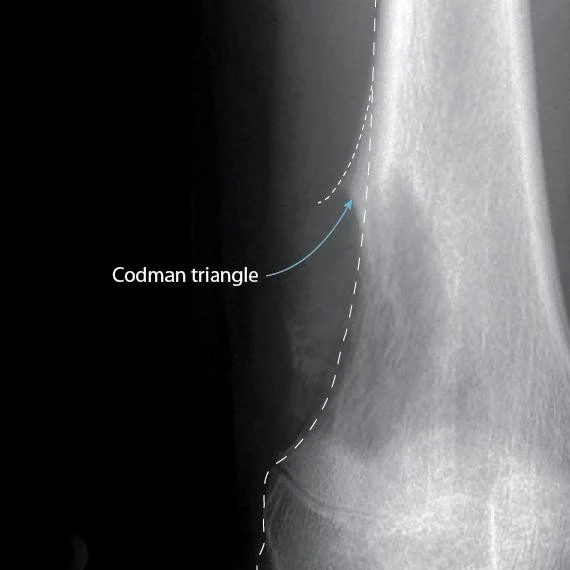

Reading Bone - Periosteal Reaction and Destruction

- Lamellated / Sun-burst / Codmanâs triangle

Type of Periosteal Reaction

- Codman triangle

Codman Triangle